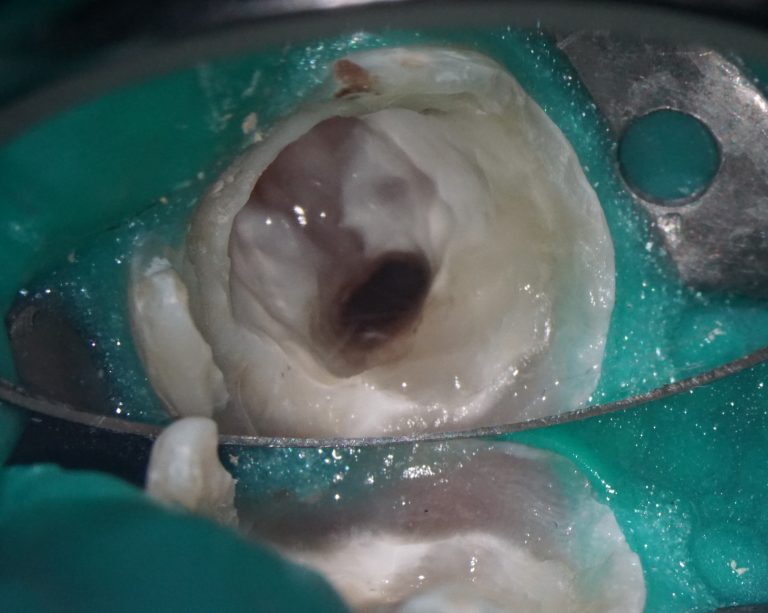

Solution: The automated process of segmentation and formation of 3D models from DICOM files allows extracting individual structures for subsequent 3D printing. The printed model of the third molar, taken from the “STL” module of Diagnocat, is used to prepare the socket for the transplanted tooth. The 3D reconstruction generated using Diagnocat displays the structure of the jaws and teeth and enables the visualization of tooth 37 (Universal 18) with periapical lesion around the roots. In this case, Diagnocat serves as a communication tool that helps convince the patient of the importance of timely implementation of the proposed treatment plan.